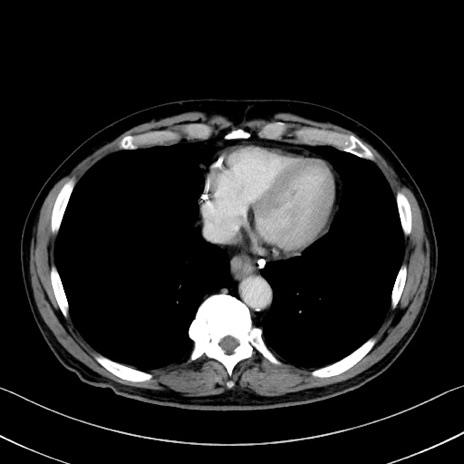

症例35(横断像)

【症例】70歳代 男性

【主訴】腹部膨満、嘔吐

【現病歴】昨日より腹部膨満感出現。本日増悪し、仙痛出現。嘔吐あり、受診。

【既往歴】糖尿病、胆摘後

【身体所見】BP 149/80mmHg、HR 74/min、BT 35.9℃、腹部:膨満、軟、圧痛なし。腸雑音減弱あり。上腹部正中切開瘢痕あり。

【データ】WBC 13500、CRP 1.72